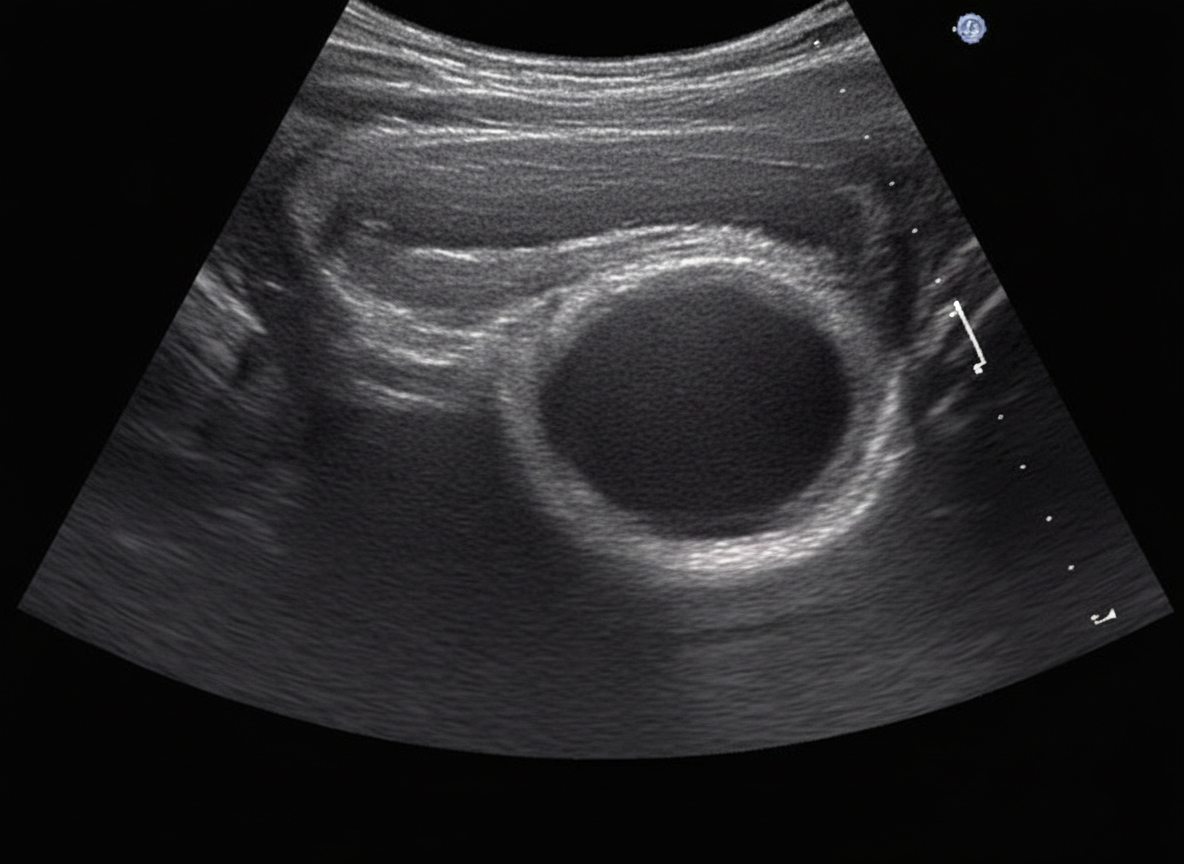

A 24-year-old female patient presents with bilateral breast mass. On physical examination this breast mass is hyper mobile and soft. The mammogram is shown below. What is the most possible diagnosis?

Explanation: ***Fibroadenoma*** - The patient's age (24 years old), bilateral location, **hypermobile** and **soft** mass on physical examination, together with the typical appearance on mammogram (well-circumscribed, oval lesion with calcifications) are characteristic of a **fibroadenoma**. - Fibroadenomas are **benign solid tumors** most common in young women, often appearing as distinct, movable lumps. *Breast cyst* - While breast cysts can be soft and mobile, they are typically **fluid-filled** and would appear as a **smooth, anechoic (dark) lesion on ultrasound**, not necessarily with dense calcifications seen on mammography. - Cysts are often associated with hormonal changes and can fluctuate in size; the described mass is solid on imaging evidence provided. *Ductal carcinoma in situ* - **Ductal carcinoma in situ (DCIS)** is a non-invasive form of breast cancer often presenting as **microcalcifications** in a linear or branching pattern, or as a mass with irregular margins. - The described mass is hypermobile and soft, and the mammographic appearance of the lesion in the image provided are not typical of DCIS which usually has spiculated margins and irregular shape. *Lobular carcinoma* - **Lobular carcinoma** (in situ or invasive) often presents as architectural distortion, an area of thickening, or as an insidious mass that is **poorly defined** and **difficult to detect** clinically or mammographically. - It is known for its "stealth" nature, often not forming a palpable lump or a distinct mass with the well-defined borders and hypermobility described. *Phyllodes tumor* - **Phyllodes tumors** are rare fibroepithelial tumors that can present as mobile breast masses in young women, but they typically grow **rapidly** and are often **larger** (>3-5 cm) at presentation. - The **bilateral** presentation and **typical mammographic appearance** favor fibroadenoma, as phyllodes tumors are usually **unilateral** and may show heterogeneous density with areas of necrosis or cystic change.